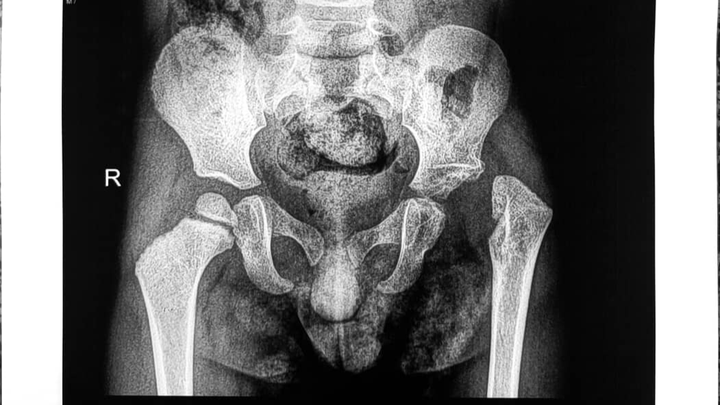

Das Kind / Mahd Mazen Mokhtar Ali, dreiundeinhalb Jahre alt, leidet unter dem Fehlen des linken Oberschenkelkopfes infolge von Folgen einer eitrigen Entzündung des linken Hüftgelenks. Dies hat zu einer Instabilität des Gelenks sowie zu einer Verkürzung der unteren Extremität geführt, bedingt durch das Fehlen der oberen Wachstumszone des Oberschenkelknochens.

الطفل / مهد مازن مختار علي والبالغ من العمر ثلاث سنوات ونصف يعاني من غياب لرأس عظمة الفخذ الأيسر ناتج عن عقابيل التهاب صديدي بمفصل الحق الأيسر مما نتج عنه عدم ثبات بالمفصل مع قصر بالطرف السفلي نتيجة غياب مركز النمو العلوي لعظمة الفخذ. والمريض يحتاج إلى جراحة ميكروسكوبية لنقل رأس عظمة الشظية مصحوبة بمركز النمو والممدودة بالأوعية الدموية، وتكلفة الجراحة حوالي 10000$، فقط عشرة آلاف دولار., وهو ما يعادل 8600 يورو تقريبا.